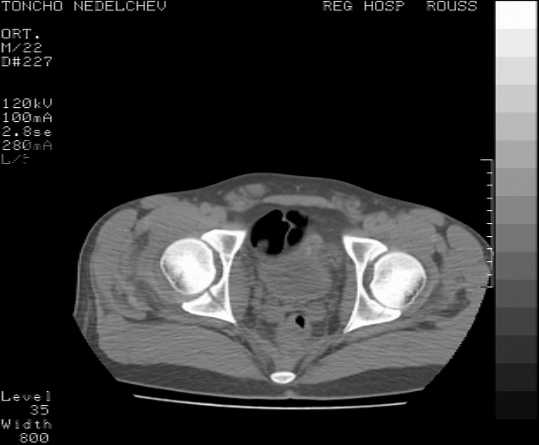

The details of the fracture are not so clear from the images sent...would you be able to send along an AP and Judet images as well as some additional axial images above and below the joint?

I’m not so sure that your patient has a Tr+PW pattern based on the images sent...maybe the fracture’s exact name won’t matter in the long run, but it’d be great to see enough images to make an accurate comment.

Here are some more axial images. What is your opinion as for the timing of the operative treatment?